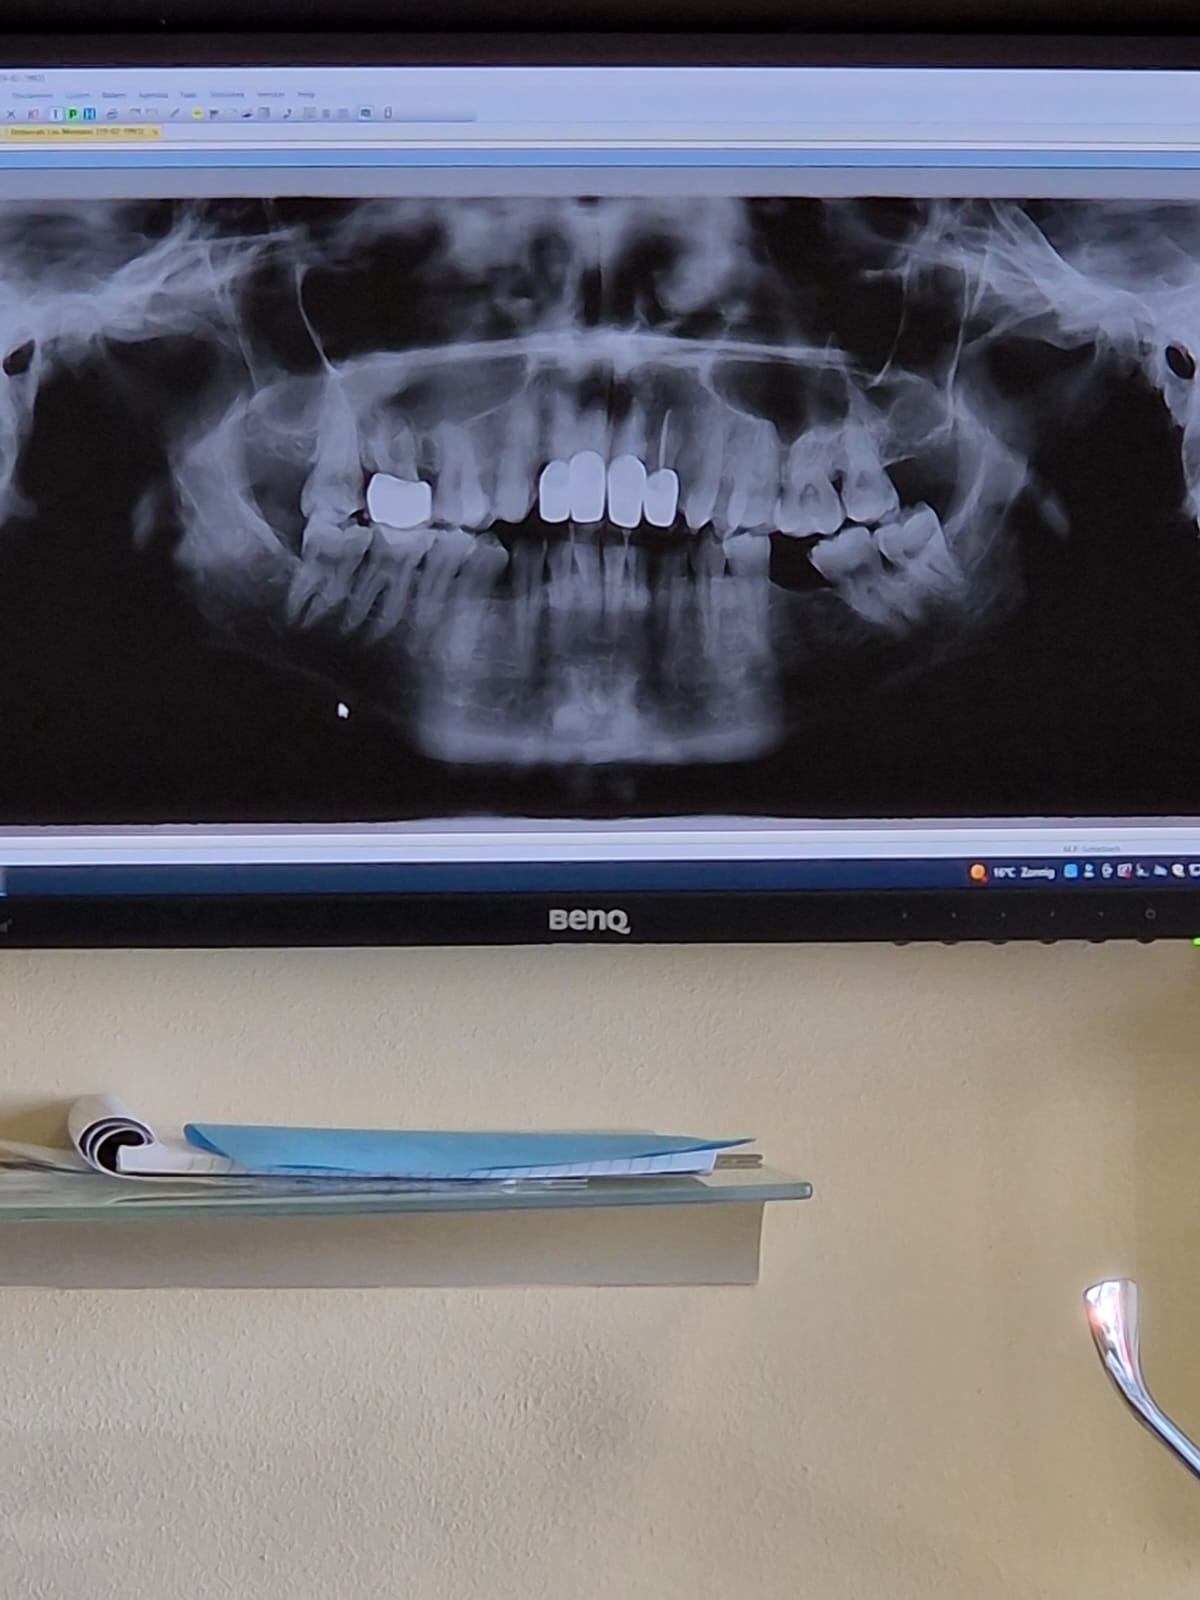

De incisale (snijlijn) komt nu beter overeen met uw oorspronkelijke stand. U trekt uw lippen nu in een gedwongen onnatuurlijke stand waardoor alles er ook anders uit ziet. De Cervicale grens( bovenkant tegen tandvlees) is iets anders dan oorspronkelijk maar dat kan gebeuren afhankelijk v hoeveel men heeft weg geslepen. u trekt uw lip ook hoger op, hoger dan dat het in een normale stand zou zijn. Als uw lip normaal zou hangen denk ik dat u niet zult zien dat de cervicale lijn zo hoog zou zijn. Ik zou een half jaar wachten met definitief cementeren v d kronen, en pas als u helemaal tevreden en klachtenvrij bent def cementeren. Ik schrik dat een tand getrokken is bij het verwijderen v d kronen. Vraag mij dan ook af of uw parodontium ( ophanging tandvlees) wel gezond genoeg is om kronen te rechtvaardigen. Zou dan ook de x-foto v voor aanvang behandeling willen zien. U kunt een kopie digitaal vragen. Bij het afmaken v d wkb worden nieuwe x-foto gemaakt, vraag die dan ook gelijk en de x-foto v d dienst. Ben benieuwd wat er op te zien is.

Dit is de foto op de zelfde dag gemaakt voordat de kronen eraf gehaald werden. Hij gaf vooraf aan niet te kunnen zien of er iets mis is met de tand. Tijdens het wegslijpen van de definitieve kronen gaf hij aan dat het inderdaad flink mis is met die tand en uiteindelijk gaf hij aan dat de tand is mee gekomen en dus weg is. Als hij de eerste keer had geluisterd toen ik aangaf een foto te maken had het wellicht voorkomen kunnen worden.

Tandarts_Richa…

Op deze foto is het voor mij niet duidelijk te zien. Zijn er ook solo foto's v d voortanden v voor ze zijn beslepen. Bent u nu de 21 kwijt?. Bent u bij de parodontoloog onder behandeling of behandeling geweest gezien het bot verlies op de foto. Op deze foto is het niet duidelijk te zien voor mij maar er lijken meer probleem punten te zijn. Zou dus graag de foto willen zien voordat de tanden beslepen zijn.

Ik ben de 11 kwijt.. Dat was mijn beste tand. De 21 was door de ontstekingen aangetast, gezak en los komen te staan. Daar is een wortelkanaalbehandeling uitgevoerd. De 11, wat nu weg is. Had ik meteen na het plaatsen van de eerste definitieve kronen last, tandarts weigerde na fotos te maken. Volgens hem kwamen de klachten door de 21. Twee weken later kwam dus de 11 eruit met het verwijderen van de kronen. Er zijn vooraf geen foto's gemaakt geworden. De uitvoering is allemaal door mijn eigen tandarts gedaan en bij een dienstzijnde tandarts is de voorbehandeling van de wortelkanaalbehandeling gedaan omdat mijn tandarts toen niet zat.

Het is jammer dat vooraf geen x-foto gemaakt is. Op deze foto kan ik niet goed beoordelen of de voortanden geschikt waren om kronen op te maken. Ik maak altijd foto's om te beoordelen voordat ik een kroon maak. Als ik het goed begrijp is in de 21 de wkb gedaan. En mijn vraag over de parodontoloog....